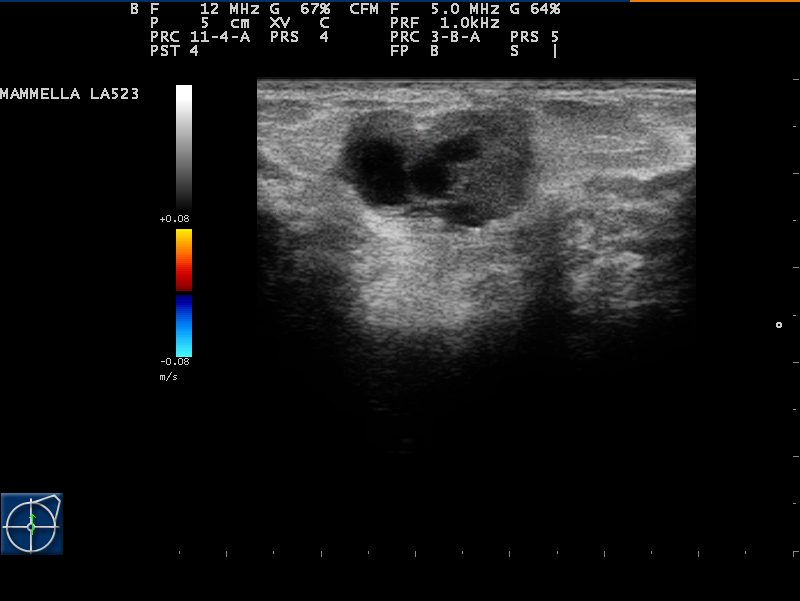

The typical ultrasound signs of fibroadenoma are as follows:

• Solid mass, frequently having homogeneous structure;

• Iso- or hypoechoic with clear contours and smooth or lobulated borders (depends on the morphological type);

• Horizontal orientation;

• Movable when compressed by the US probe;

• Occasionally, dorsal pseudo-amplification of the signal may occur;

• Hypo- or avascular while mapping in CDI (color Doppler imaging) and PD (power Doppler) modes;

• Strain-ratio index at elastometry is above 2.5.

Breast fibroadenoma on ultrasound image

Breast fibroadenoma on ultrasound image. Author: Dr. Taco Geertsma. Source: UltrasoundCases [12]